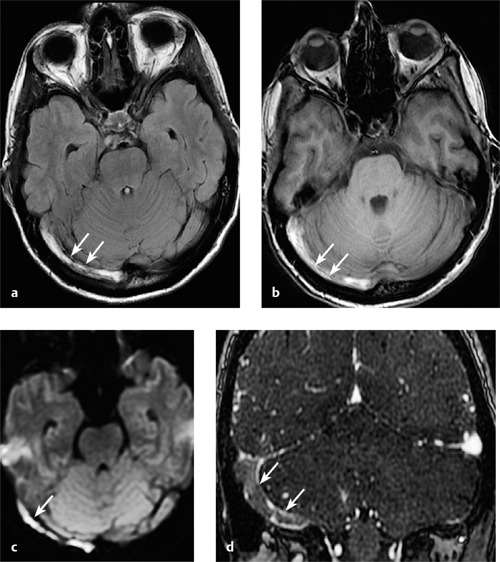

원래 뇌정맥혈전증은 신경과 뇌혈관 클리닉에서 그리 흔한 질환은 아닙니다. 성인에서 1년에 100만 명 당 2-5명 정도입니다. 보통 뇌혈관 질환은 대부분 동맥에서 발생하고, 정맥에서 피가 응고되어 해당 혈액순환이 저하되어 허혈 혹은 출혈이 생기는 정맥혈전증은 드뭅니다. 뇌정맥혈전증이 생기면 피떡도 차있고, 세포괴사로 부종과 뇌출혈 소견도 확인됩니다.

혈전(피떡), 세포 괴사 및 부종, 출혈이 동반된 뇌정맥혈전증 (출처 Radiologykey.com)